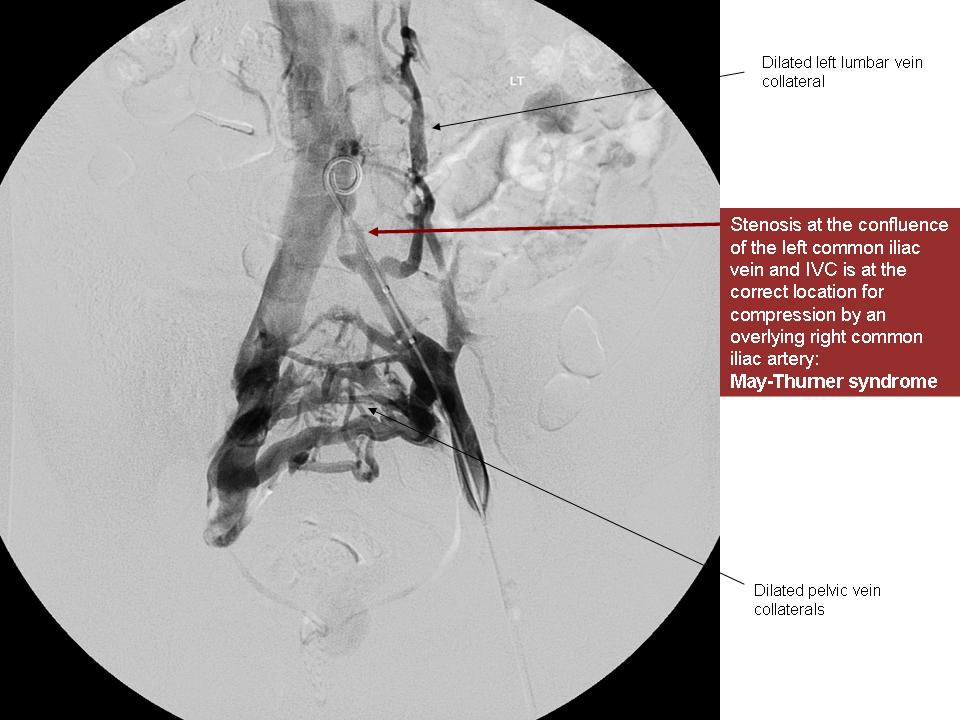

Can May Thurner Syndrome cause symptoms in BOTH legs? Get Healthy Veins Nutcracker Syndrome Venography nutcracker syndrome (ncs) is a syndrome caused by compression of the left renal vein (lrv), between the abdominal. a combination of cystoscopy, duplex ultrasonography (dus), computed tomographic venography (ctv),. It can be divided into. nutcracker syndrome (ncs) describes left renal vein compression between the superior mesenteric artery and the aorta. nutcracker syndrome refers to the constellation. Nutcracker Syndrome Venography.